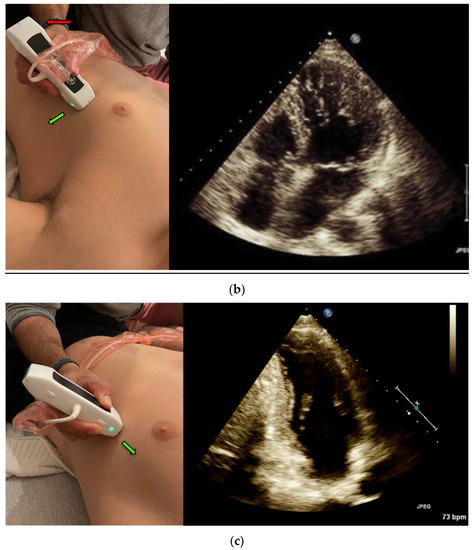

Left ventricular (LV) Ejection Fraction is an important clinical index. EF assessment can be extremely valuable in evaluating hemodynamically unstable patients [12] and dyspneic patients [4]. It can also diagnose heart failure in different settings, such as the emergency department and the internal wards [13,14]. The classic method for measuring EF is the Simpson method, which requires manually tracing the endocardial border of the left Ventricle in systole and diastole in both the apical four-chamber view (Figure 1a) and the apical two-chamber view (Figure 1c) [15].

The Velocity Time Integral (VTI) is classically measured at the apical five-chamber view (Figure 1b) by measuring the flow velocity through the left ventricle outlet (LVOT), which provides a velocity over time curve. Multiplying the VTI times the left ventricular outlet area equals the cardiac stroke volume, and if multiplied by the heart rate—the cardiac output [22]. The cardiac stroke volume aids in the differentiation of shock, shock treatment, determining fluid responsiveness, and in risk stratification [23,24]

A POCUS expert acquired apical four-chamber view (A4CV) clips by placing the probe horizontally over the apex of the heart (Figure 1a) and prospectively recording for at least 10 s. All clips were reviewed and blindly assessed for LVEF quantification by the Expert without exposure to the automatic tool results. Post hoc automatic analyses were performed and documented using the Venue™ real-time automatic LVEF. Each clip was considered an independent observation point.

5. VTI Measurement

An expert POCUS operator acquired the views by placing the probe horizontally in the apex of the heart and prospectively recording for at least 10 s in the apical five chambers view (Figure 1b). Half of the clips were scored by the physician to quality distribution from zero to two: 0—low for a failed attempt to obtain a proper reading of the VTI or image that could not be analyzed, 1—medium for VTI can be calculated but with moderate imaging quality and 2—high for good quality clips with a clearly demonstrated VTI. The clips were then blindly measured, tracing the LVOT velocity curve manually for VTI. The automatic tool measured the same clip, which similarly scored the clips according to imaging quality. High- or medium-quality clips were then further assessed and automatically calculated for LVOT VTI values. Each clip was considered an independent observation point.

Figure 1. (a) Acquisition and anatomy of the Apical Four Chamber View. (b) Acquisition and anatomy of the Apical Five Chamber View (similar acquisition to Apical Four Chamber View, with a slight upward tilt of the probe). (c) Acquisition (probe point—green arrow) and anatomy of the Apical Two Chamber View.